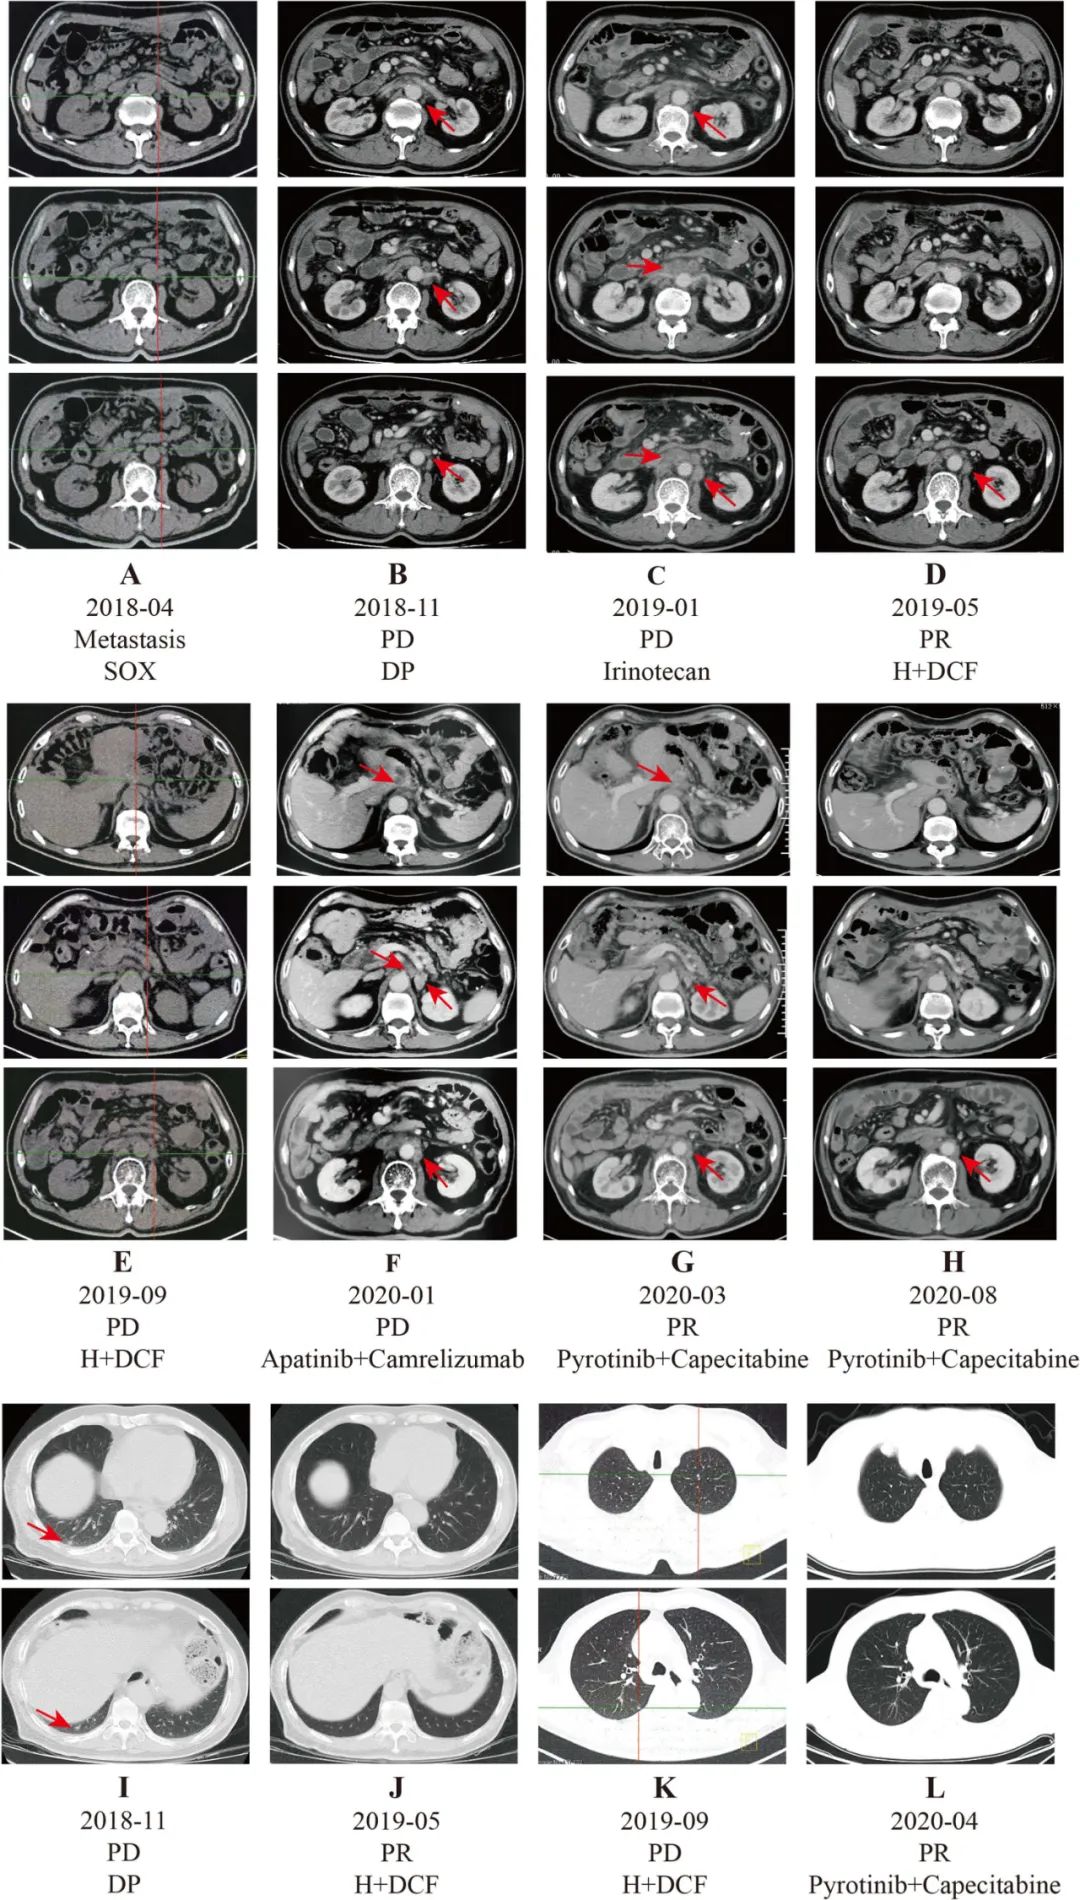

患者术后辅助治疗期间出现进展,因此术后辅助化疗被认为是一线化疗,目前应行二线治疗。因患者术后病理提示HER2(3+),建议予曲妥珠单抗联合化疗。患者因经济原因拒绝使用曲妥珠单抗,故2018-60-20起予患者DP(多西他赛+顺铂)方案化疗,每三周重复,共6周期。期间每2周期复查上腹部增强CT均提示腹腔淋巴结病灶稳定(SD)。2018年11月复查肿瘤标志物CEA:49.1ng/mL,CA19-9:8078U/mL。胸部+腹部CT:右肺下叶小结节,考虑新发转移灶可能;胃癌术后,后腹膜多发肿大淋巴结,较前相仿。

患者经过两线化疗后,一般状态良好(PS评分0分),血常规、肝肾功能基本正常,建议患者更换化疗方案,于2018-11期行伊立替康单药方案化疗,2019-01复查上腹部CT提示疾病进展(PD),CEA:65.6ng/mL,CA19-9:16644U/mL。

2019年后曲妥珠单抗纳入上海医保范畴,故建议患者曲妥珠单抗联合化疗。患者2019-01开始行曲妥珠单抗+DCF方案(多西他赛+顺铂+5-Fu)方案治疗。经2个周期治疗后,腹部CT显示腹膜后淋巴结部分缓解(PR)。4个周期治疗后,胸部CT示肺转移消失,腹部CT示腹膜后淋巴结PR。2019年9月PET-CT示左、右肺新结节,腹膜后多发肿大淋巴结。最大淋巴结长度约2.4 cm,最大SUV为10.75。CA199 (3988.0 U/mL)和CEA (30.2 ng/mL)显著升高。综合考虑,患者病情进展。

晚期胃癌患者经过第四线治疗后,已无标准的治疗。我们建议进行基因检测,患者拒绝。综合考虑,给予抗血管生成(阿帕替尼)联合抗PD-1抑制剂(卡瑞利珠单抗)治疗。经过两个周期的治疗后,腹部CT扫描显示病灶稳定。之后,我们又给病人进行了两个周期的治疗。2020年1月CT示腹膜后淋巴结略增大,CA199 (13725.0 U/mL)、CEA (48.3 ng/mL)明显升高。

患者病情进展后行基因检测。NGS测序结果示HER2基因拷贝数增加,HER2基因未发生突变。基于新型HER2靶向药物吡咯替尼与卡培他滨联合治疗可用于曲妥珠单抗耐药的乳腺癌患者。因此,患者于2020年1月行吡咯替尼联合卡培他滨治疗。三个周期后,腹部CT扫描显示腹膜淋巴结PR。四个周期后,胸部CT扫描显示肺结节消失。与此同时,CA199和CEA呈稳步下降趋势。2020年8月腹部CT示腹膜后淋巴结PR。患者对吡咯替尼治疗耐受良好,未观察到不良事件。PFS超过11个月。

图1. 患者治疗期间影像学评估资料变化情况